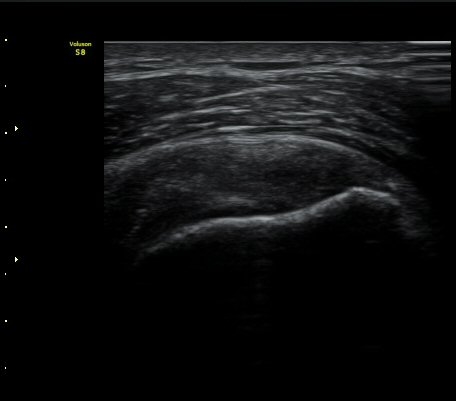

±Ø»ó°Ç Á¾´Ü¸é°Ë»ç½Ã ±Ø»ó°Ç ºÎÂøºÎ¿¡ Àú¿¡ÄÚ ºÎÁ¾°ú ¹Ì¼¼ÇÑ °Ç ¿¬°á¼º ¼Ò½ÇÀÌ

°üÂûµÊ (±×¸² 1, 2, 3 )